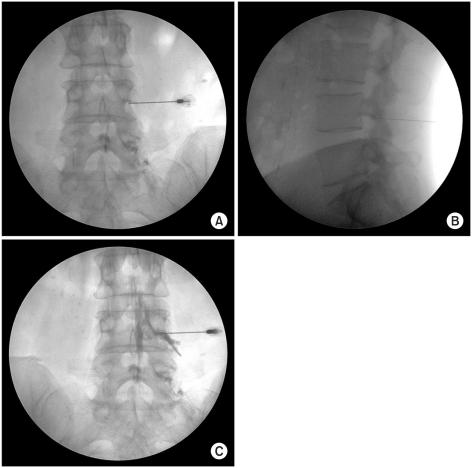

Fifty patients with lumbar radicular pain from lumbar spinal stenosis and herniated lumbar disc were enrolled. Subjects were randomly assigned to one of two groups (CL or PL group). All procedures were performed using a C-arm (KMC 950, KOMED, Kwangju, Kyunggi, Korea). We compared the frequency of complications during the procedure and the effects of the pain block between the two groups at 2, 4, and 12 weeks after the procedure.

There were no significant differences in the demographic data, initial VNS (Visual numeric scale), or ODI (Oswestry disability index) between the CL group (n=26) and the PL group (n=24). There was no statistically significant difference in the outcome measures (VNS and ODI) between the groups at 2, 4, or 12 weeks. Symptoms of nerve root irritation occurred in 1 case of the CL group and in 7 cases of the PL group (p<0.05). Pricking of spinal nerve during the procedure and transient weakness after the procedure occurred in 6 cases and 3 cases, respectively in the CL group, but did not occur in the PL group.

Our findings suggest that the posterolateral approach represents an alternative TFESI method in cases with difficult needle tip positioning in the anterior epidural space, and could lower the risk of target nerve root irritation and nerve penetration.